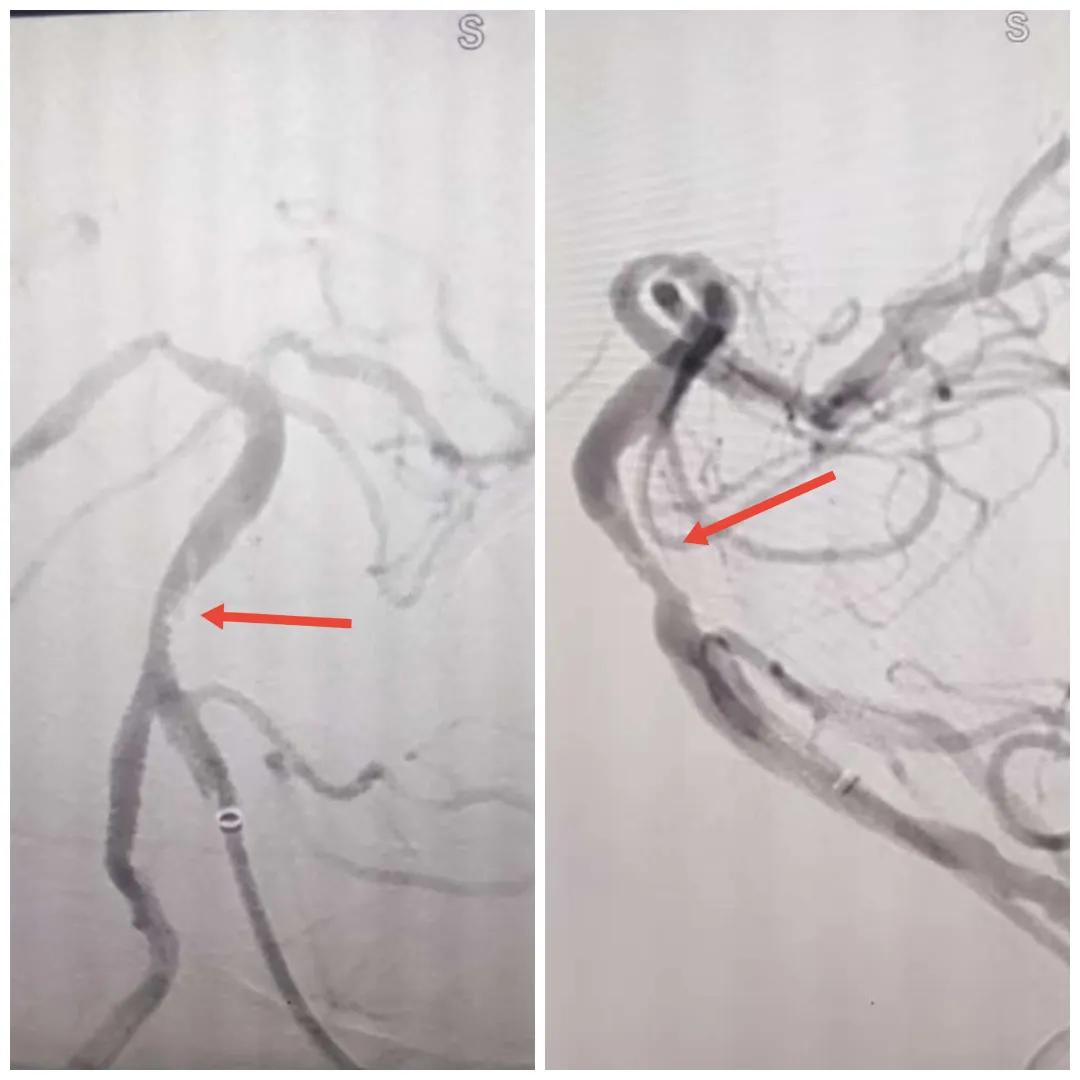

在經(jīng)造影后,主刀醫(yī)生腦一科副主任楊慶堂發(fā)現(xiàn)患者基底動脈下段重度狹窄且狹窄段以遠有大負(fù)荷血栓,其狹窄處考慮為動脈夾層,手術(shù)難度及風(fēng)險較大。楊慶堂副主任在彭壯副主任醫(yī)師的協(xié)助下運用spaceman(太空人)技術(shù),中間導(dǎo)管抵近血栓抽吸配合支架拉栓,成功開通血管。再次造影可見基底動脈管腔明顯增寬,遠端血管顯影良好,且等待20分鐘后造影仍顯示血流通暢。楊慶堂副主任考慮到本次手術(shù)時間不宜過長,現(xiàn)患者基底動脈及分支前向血流維持良好,給予其抗栓藥物應(yīng)用后結(jié)束手術(shù),并建議患者3個月后復(fù)查造影,明確其基底動脈夾層情況。

造影可見血管夾層和大量血栓形成

取栓后血管管腔增寬,前向血流良好